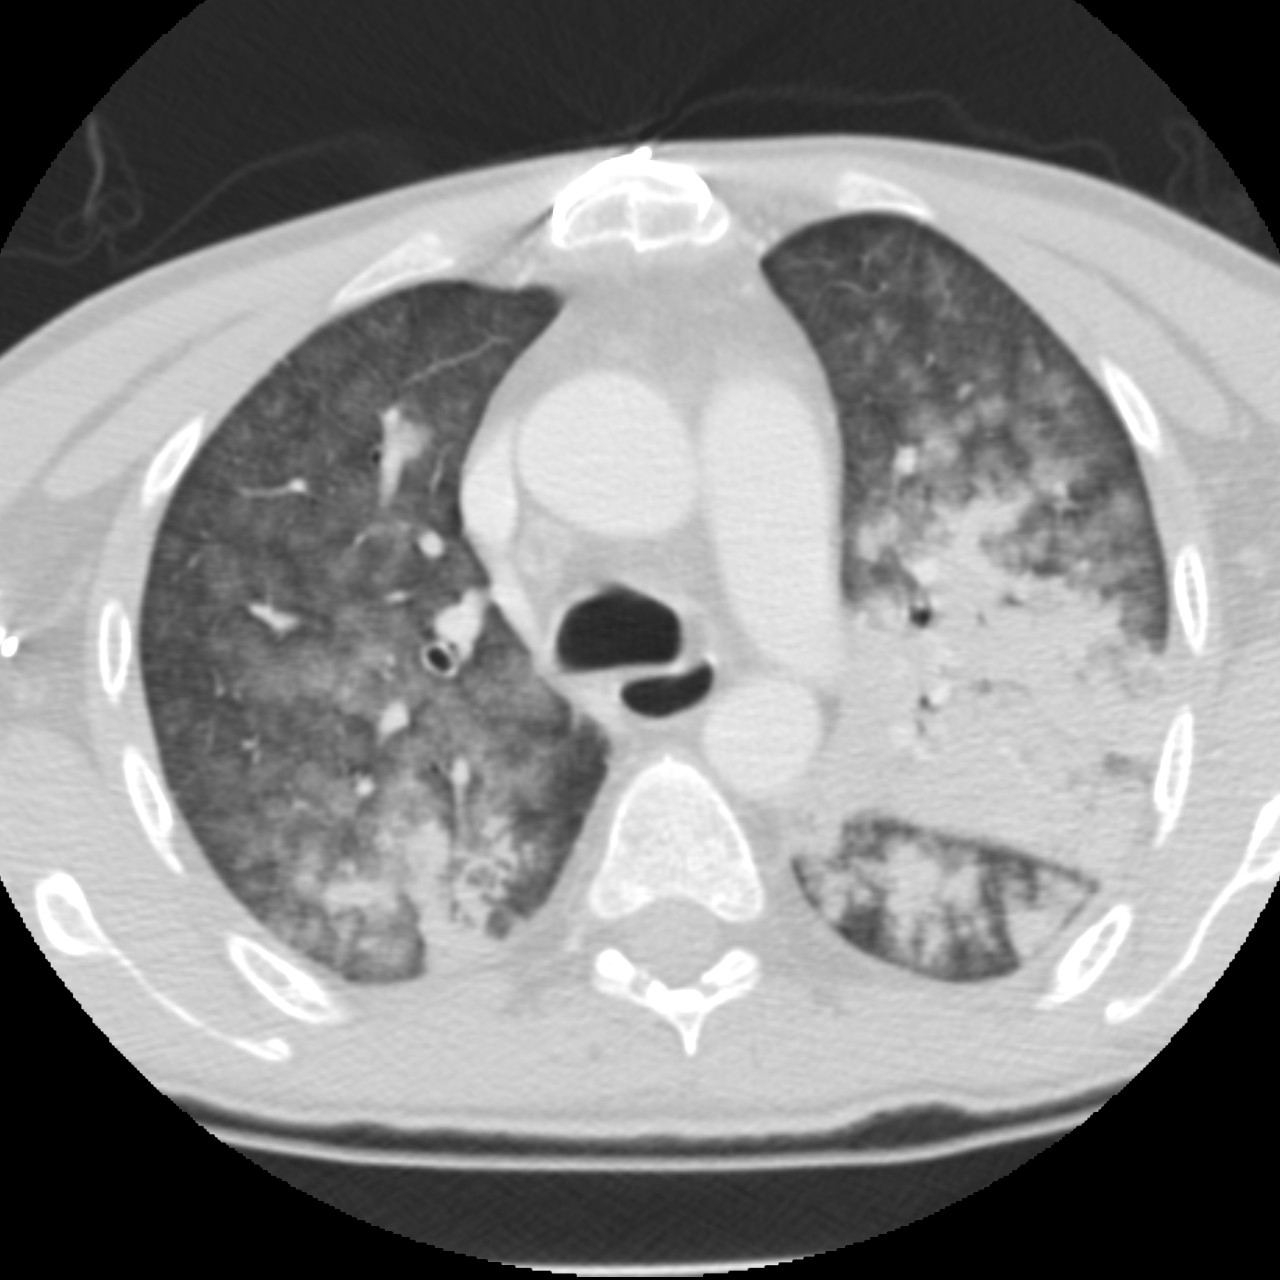

Discover the function of the Pores of Kohn, the small openings in the alveolar walls of the lungs. Learn how these inter-alveolar communications facilitate collateral ventilation, maintain pulmonary pressure, and play a crucial role in gas exchange, potentially aiding in the spread of pneumonia within the lung parenchyma. Enhance your understanding of respiratory anatomy and pulmonary physiology today.